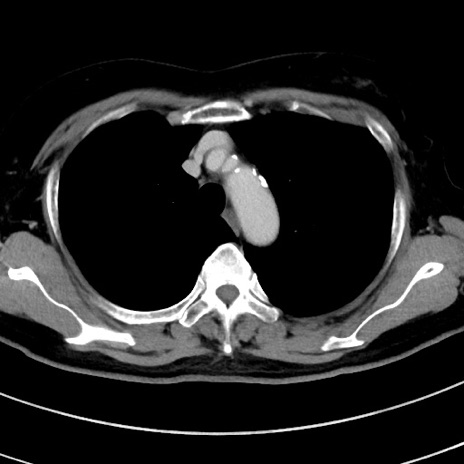

冠状断像

【症例】 60歳代女性

【主訴】むかつき、みぞおちの痛み

【現病歴】3日前よりむかつきがあり、食事がとれない。

【既往歴】糖尿病

【身体所見】発熱なし、心窩部圧痛軽度あるも、腹膜刺激症状なし。

【データ】WBC 7400、CRP 1.92